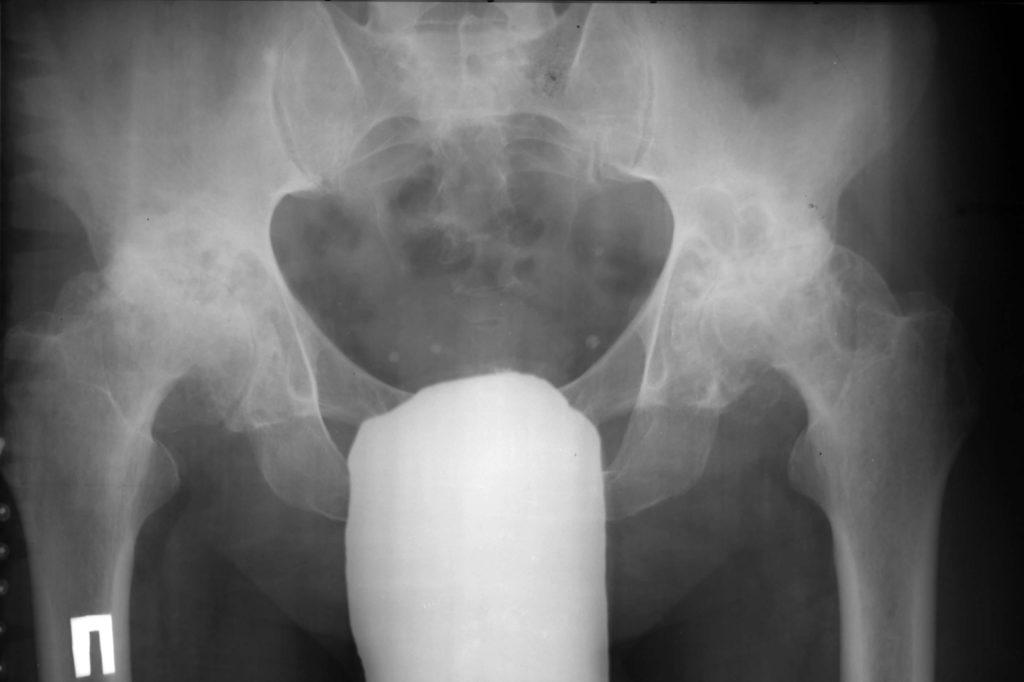

УЗИ, рентген и МРТ тазобедренного сустава обязательно при диагностировании артрозо-артрита

- рентген тазобедренного сустава,

Рентген тазобедренного сустава позволяет выявить степень поражения костной и хрящевой ткани, а также точную локализацию и распространение патологического процесса.